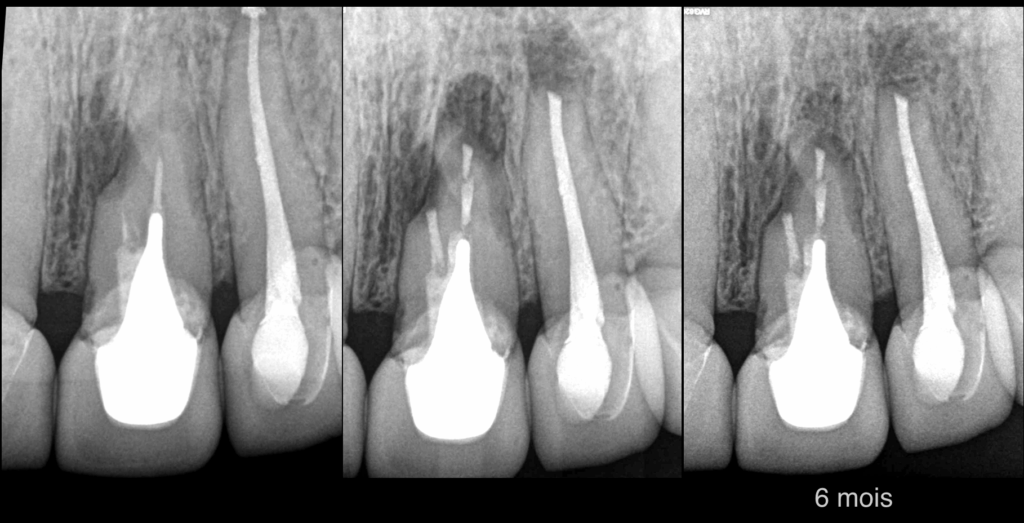

📆 𝐀̀ 𝟔 𝐦𝐨𝐢𝐬, 𝐥𝐚 𝐜𝐡𝐢𝐫𝐮𝐫𝐠𝐢𝐞 𝐞𝐬𝐭 𝐞𝐟𝐟𝐢𝐜𝐚𝐜𝐞 𝐩𝐨𝐮𝐫 𝐥𝐞𝐬 𝟐 𝐝𝐞𝐧𝐭𝐬.

📅 Prochain contrôle dans 6 mois pour les 1 an.